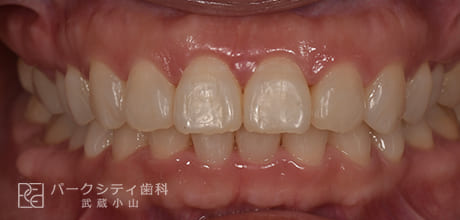

CASE.02

表側の部分矯正の症例

術前

術中1か月

術中3か月

4か月

- 主訴

- 前歯の隙間が気になる

- 治療法

- 表側の部分矯正

- 治療期間

- 4か月

- 費用

- ¥413,600

【内訳】

検査料:¥33,000

装置料:¥165,000×2(上下)

チェック:¥4,400×4

保定装置:¥16,500×2(上下)

上下表側に装置をつけ、隙間を閉じながら歯並びを整えて、約4か月で保定へ移行しました。